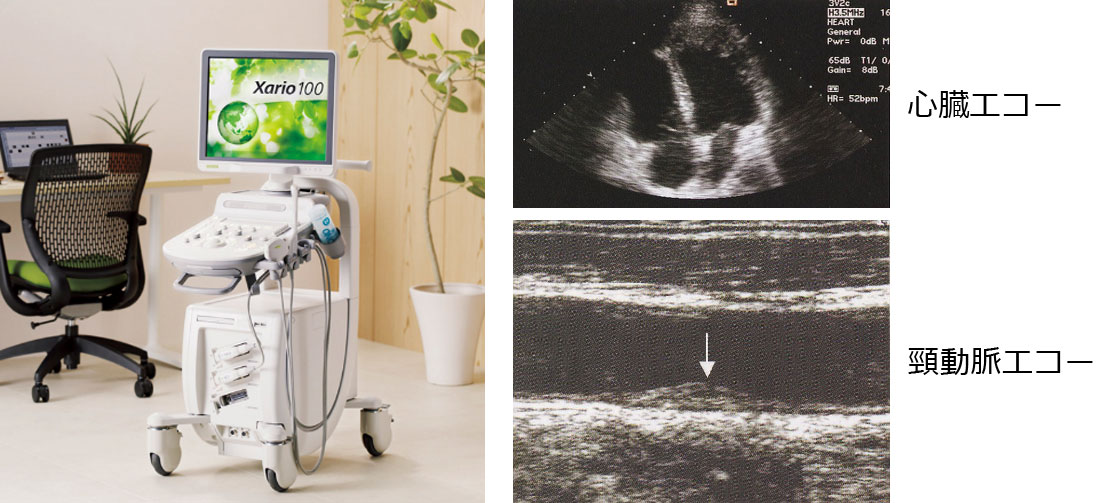

- 超音波(エコー)検査(心臓・腹部・頸動脈)